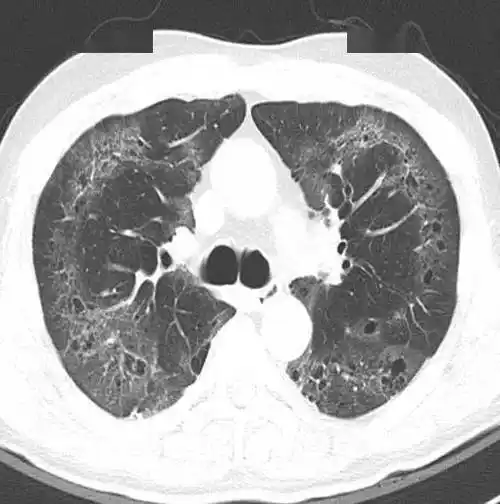

间质性肺炎

间质性肺炎的典型图谱最全解析

间质性肺炎(interstitial pneumonia)